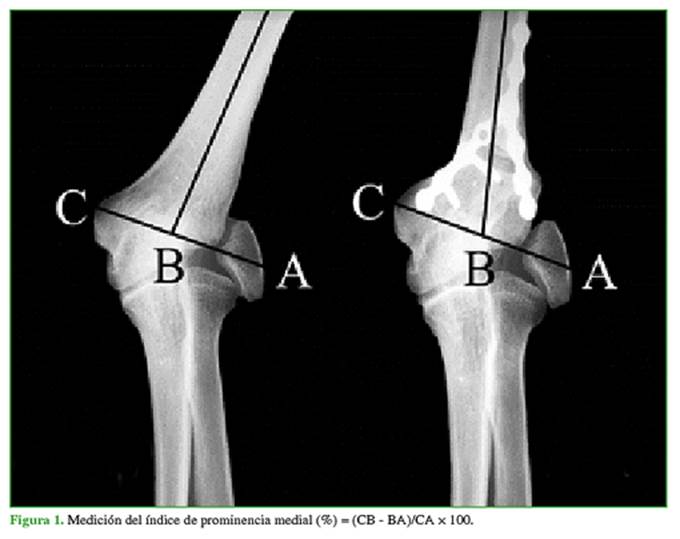

La prominencia medial se midió con la escala de Wohn9 (Figura 1).

La evaluación radiográfica preoperatoria arrojó un valgo promedio de 30º (rango 22-40°), con un valgo con-tralateral de 11º (rango 5-20°). La corrección radiográfica mostró un valgo de 13º. Por lo tanto, se obtuvo una corrección, en promedio, de 2° menos que del lado contralateral. Todas las osteotomías consolidaron y la medición de la prominencia medial fue, en promedio, un 32% (rango 13-54) mayor que en el preoperatorio (Figuras 2 y 3).